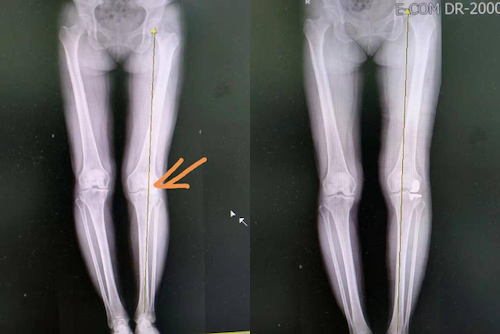

女,56岁,左膝关节疼痛4年,诊断为左膝关节膝外翻,全长片显 - 抖音

图片尺寸1440x1920